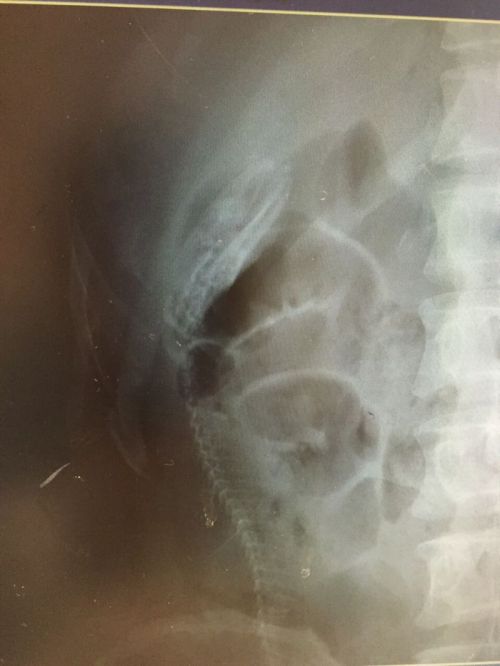

gif_animation ウナギでアナルオ●ニーしていた男の恐ろしい末路。男はお腹(腸内)に激しい痛みを訴え、病院を訪れた。それは手術により取り出され…。[4]images